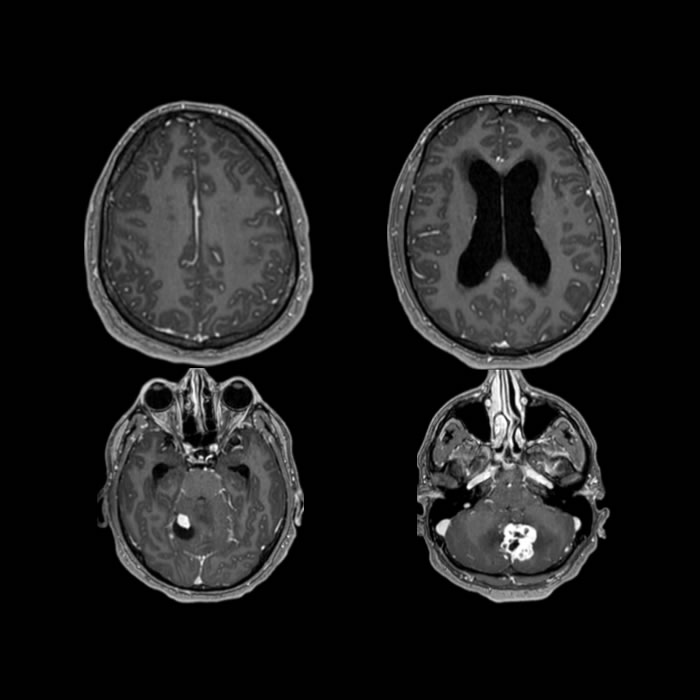

Noviembre 2023. Sanatorio Allende Paciente masculino de 33 años que ingresa por GC con cuadro de cefalea, visión borrosa y mareos de tres semanas de evolución.